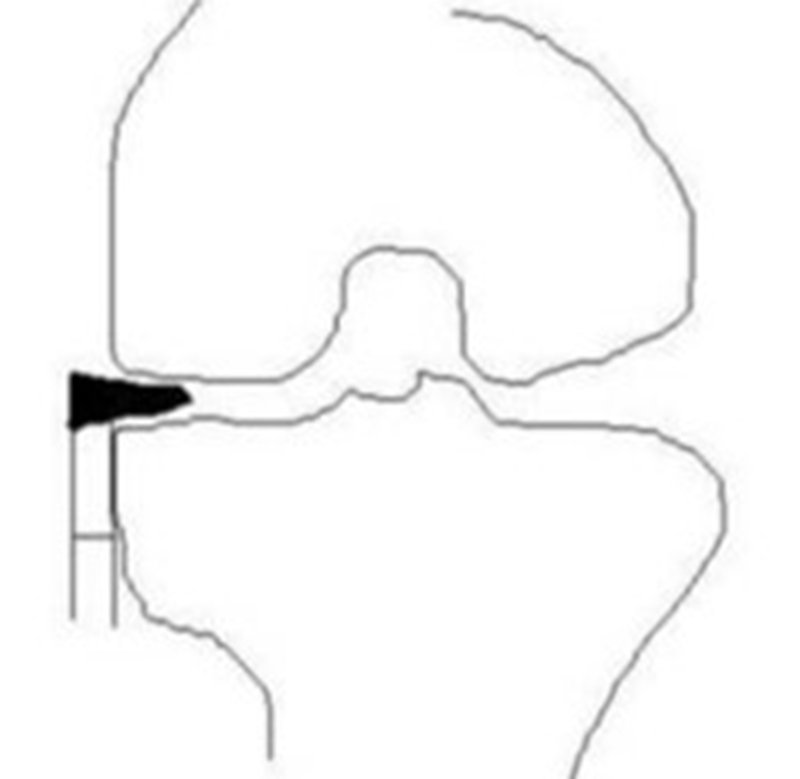

③应力源性理论:

关于SONK与内侧半月板损伤,在一项研究中,关节造影检查27个SONK膝关节中发现有21个(78%)半月板撕裂,半月板碎片边缘的应力集中可能导致股骨髁缺血性坏死。

表明老年患者通过关节造影早期发现内侧半月板撕裂并及时治疗,对于避免“自发性”骨坏死的晚期变化可能很重要。

另一项研究纳入26篇文章,其中有21篇(80.7%)涉及半月板在SONK发展中的作用,启示SONK与半月板撕裂或半月板切除术后的发展有关,而内侧半月板撕裂、后根撕裂更常见。

SONK与内侧半月板后根部损伤,有国外学者在SONK患者中通过MRI及关节镜检查,常可发现合并内侧半月板后根部的撕裂,该发生率可达到80%(24/30), 15例完全撕裂,9例部分撕裂。结果表明SONK可能与内侧半月板后根部撕裂后,导致股骨负重区的应力集中、软骨下骨髓水肿有关。

对于半月板损伤类型对SONK的影响,一项研究结果显示内侧半月板后根部撕裂组的半月板突出率为46.1%,平均坏死面积为423.1mm2。内侧半月板后角水平裂组的半月板突出率为35.3%,平均坏死面积为175.8mm2。

与内侧半月板后角水平撕裂相比,后根撕裂将导致更大程度的突出和更广泛的骨坏死。

SONK与内侧半月板突出的相关研究中,100%(104)SONK中都有半月板突出,4个SONK在发病前因膝关节疼痛体检发现半月板突出,几个月后通过MRI检查显示存在 SONK。

研究证明半月板挤压是SONK的发病机制之一,半月板挤压的进展可能与SONK的发展有关。

关于SONK与下肢力线的关系,一项研究结果显示SONK组MPTA畸形比OA组更大,高达约1.5°,SONK组JLCA也显著高于OA组。

提示胫骨近端内翻畸形和膝关节松弛,有助于诱发SONK,SONK骨软骨病变的大小受胫骨近端内翻畸形的影响。临床中MPTA小于 84°且伴有急性膝关节疼痛应尽快MRI检查。

国内一项研究纳入内侧半月板损伤患者97例,男40例,女57例,年龄32~66岁,通过MRI测量半月板外突>3mm者38例,无半月板外突者59例。膝内翻患者半月板突出的发生率为89%,半月板根部撕裂患者半月板突出的发生率为78%,证明膝内翻、内侧半月板根部撕裂是造成内侧半月板突出的主要危险因素。

膝内翻 内侧半月板根部撕裂

应力源性理论